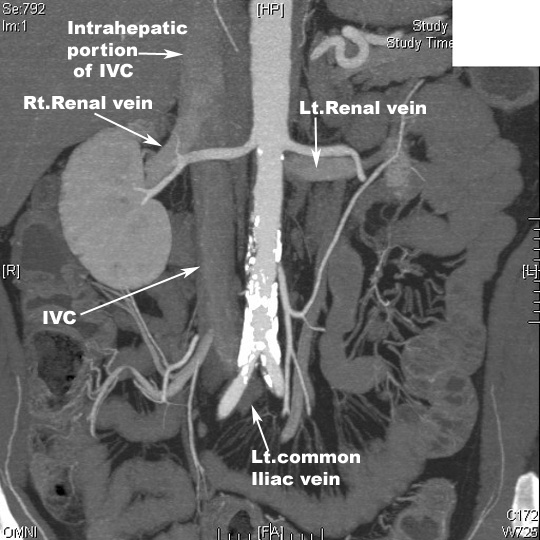

| PA view Reconstructed image | Tributaries emptying into IVC |

| Reconstructed image MRA | Tributaries emptying into IVC |

| Reconstructed image | Course of Renal veins |

| PA view Reconstructed image | Renal veins entering IVC |